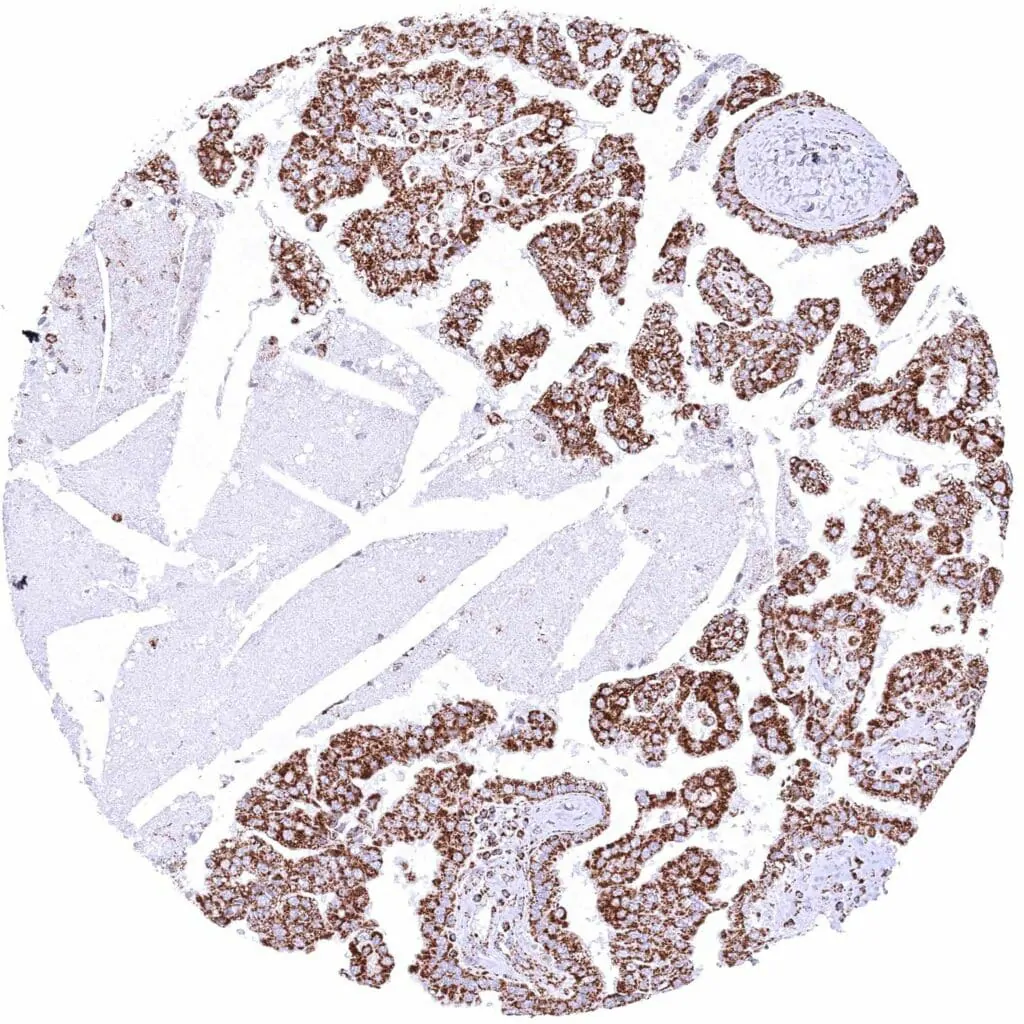

Kidney – Chromophobe renal cell carcinoma with strong cytoplasmic ATP5J immunostaining of tumor cells.